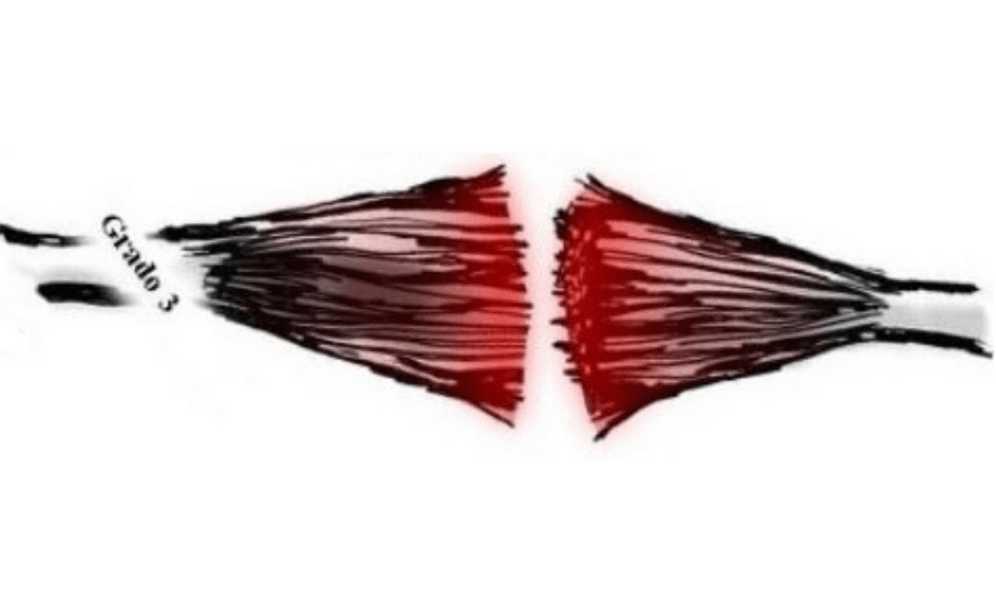

En cuanto al desgarre muscular lo podemos clasificar dependiendo de su gravedad.

Grado III:

Ruptura total de las fibras musculares.

- Dolor intenso si realizar algún movimiento

- Dificultad considerable para mover la parte afectado.

- Limitación completa dependiente de asistencia o auxiliares para realizar alguna actividad.

- Enrojecimiento.

- Inflamación considerable.

- Aumento de la temperatura.

- Puede aparecer hematoma (moretón) al dia siguiente con un diámetro muy amplio alrededor de la lesión.

Su tratamiento obligatoriamente debe ser quirúrgico para después empezar el abordaje fisioterapéutico.

Pronóstico de recuperación:

dependiente de las características de la afectación, con recuperación de un 70 a 85% después de los 6 meses